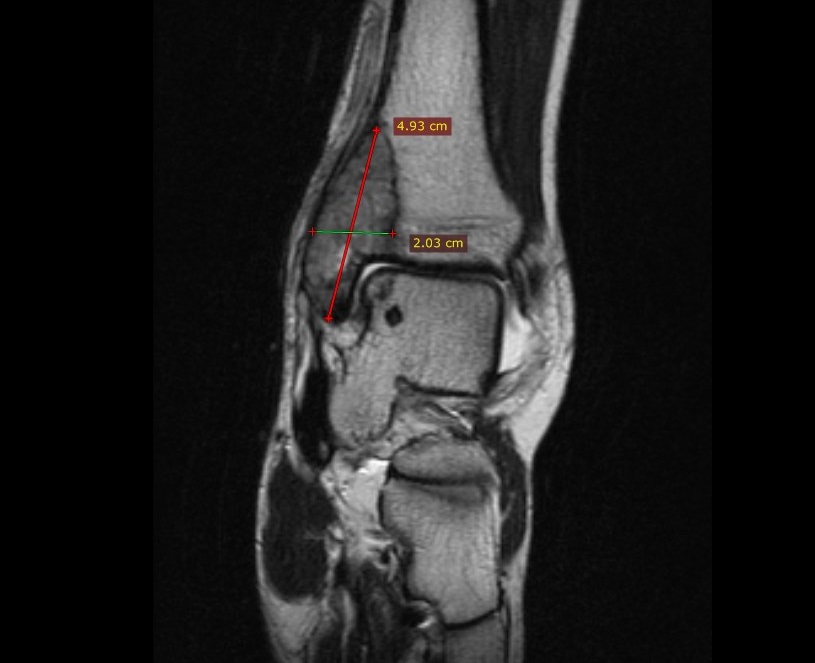

MRI (Μαγνητική Τομογραφία) γιγαντοκυτταρικού όγκου στον έσω σφυρό